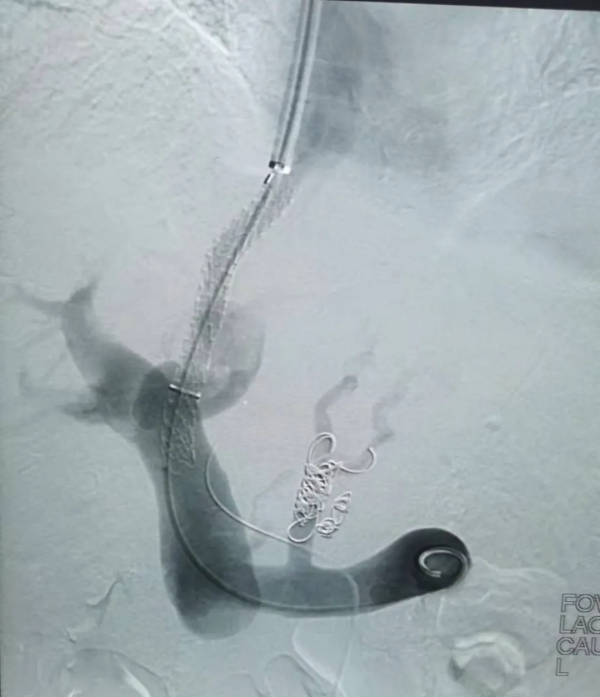

TIPSS以其創傷小和令人滿意的療效,已成為肝硬化門靜脈高壓症常用的介入治療方法。該技術是局麻下穿刺頸內靜脈,引入穿刺針,從肝靜脈向門靜脈穿刺,成功後置入導絲至門靜脈,沿導絲用球囊擴張穿刺道,置入血管支架,使門靜脈血流向肝靜脈,即肝內門體分流術,從而降低門靜脈壓力,門靜脈壓力下降了,同時還可將導管插入胃冠狀靜脈,用彈簧圈栓塞曲張靜脈,達到雙重治療作用。手術歷時三小時,非常成功。